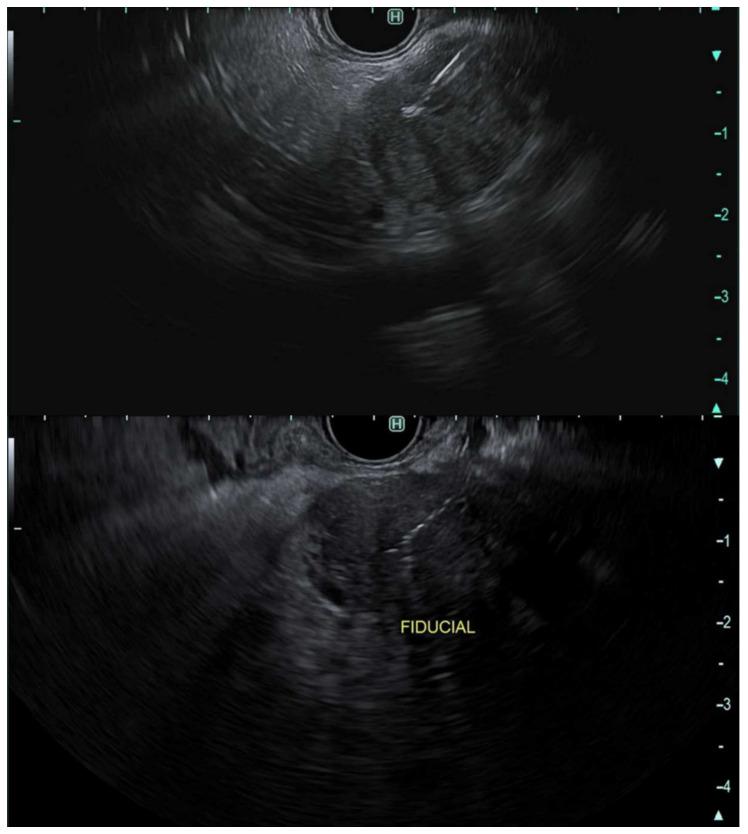

内镜超声检查在胰腺癌诊断及分期中的作用

The Role of Endoscopic Ultrasonography in the Diagnosis and Staging of Pancreatic Cancer.

Pancreatic cancer is the fourth leading cause of cancer-related death and the second gastrointestinal cancer-related death in the United States. Early detection and accurate diagnosis and staging of pancreatic cancer are paramount in guiding treatment plans, as surgical resection can provide the only potential cure for this disease. The overall prognosis of pancreatic cancer is poor even in patients with resectable disease. The 5-year survival after surgical resection is ~10% in node-positive disease compared to ~30% in node-negative disease. The advancement of imaging studies and the multidisciplinary approach involving radiologists, gastroenterologists, advanced endoscopists, medical, radiation, and surgical oncologists have a major impact on the management of pancreatic cancer. Endoscopic ultrasonography is essential in the diagnosis by obtaining tissue (FNA or FNB) and in the loco-regional staging of the disease. The advancement in EUS techniques has made this modality a critical adjunct in the management process of pancreatic cancer. In this review article, we provide an overall description of the role of endoscopic ultrasonography in the diagnosis and staging of pancreatic cancer.

胰腺癌是美国癌症相关死亡的第四大原因,也是胃肠道癌症相关死亡的第二大原因。胰腺癌的早期检测、准确诊断和分期对于指导治疗方案至关重要,因为手术切除是这种疾病唯一可能的治愈方法。即使是可切除疾病的患者,胰腺癌的总体预后也很差。有淋巴结转移疾病患者手术切除后的5年生存率约为10%,而无淋巴结转移疾病患者为约30%。影像学研究的进展以及包括放射科医生、胃肠病学家、高级内镜专家、医学、放射和外科肿瘤学家在内的多学科方法对胰腺癌的管理产生了重大影响。内镜超声检查对于通过获取组织(细针穿刺抽吸或细针穿刺活检)进行诊断以及对疾病进行局部区域分期至关重要。内镜超声技术的进步使这种检查方式成为胰腺癌管理过程中的关键辅助手段。在这篇综述文章中,我们全面描述了内镜超声检查在胰腺癌诊断和分期中的作用。